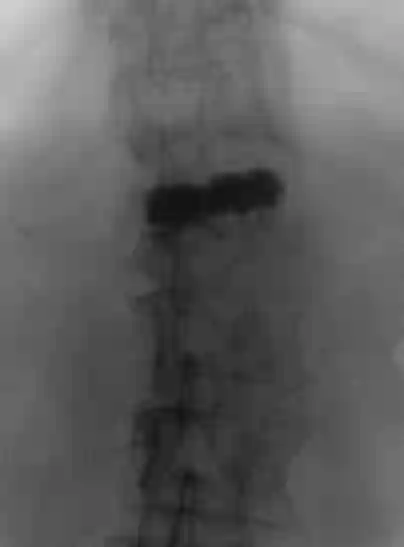

Vertebroplastie Röntgen

Laterale Röntgenansicht von LWK1 nach durchgeführter Vertebroplastie mit Knochenzement.